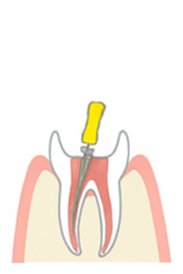

虫歯が進行して神経まで達すると、温かい物がしみたり、何もしなくても痛むことがあります。

歯の神経や感染部分を取り除く根管治療が必要となります。

マイクロスコープは、根管内を拡大し明るい状態で確認できます。肉眼では見えにくい部分も把握しやすく、感染した歯髄の除去を精密に行うことができます。

歯科用CTを用いることで、歯や根管の状態を3次元的に把握できます。根管の形やサイズは個人差があり、CTによって正確な情報を得ることで、より精密に治療できます。

根管治療後の再発率は約30〜70%といわれています。根管の先端は直径0.25mm程度と非常に細く、精密な処置には専用の機器や設備が欠かせません。

たかた歯科医院では、精度の高い根管治療を行うために、以下のような取り組みを行っています。